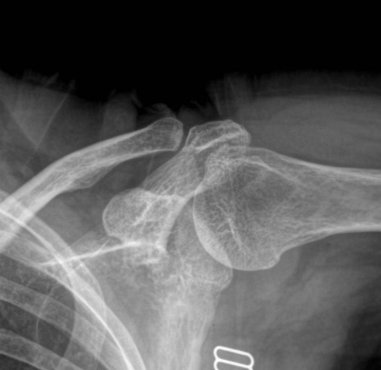

¹æ»ç¼± °Ë»ç : ¾î±ú ÀÜ¸é »çÁø¿¡¼­ ´ë°áÀýÀÇ ¹Ì¼¼ÇÑ °ñ±Ø°ú °æÈ­µÈ ¼Ò°ßÀ» º¸ÀÌ°í °ßºÀ ÇÏ´ÜÀÇ  °æÈ­ ¼Ò°ß ¹×

¿À±¸µ¹±â °ßºÀÀÎ´ë ºÎÂøºÎ °ñ±ØÀ» º¸¿© ¸¸¼ºÀûÀÎ Ãæµ¹ÀÌ ÃßÁ¤µÊ.

¿ÜÀü½Ã Àü¸é »çÁø¿¡¼­ ´ë°áÀýÀÌ °ßºÀÇÏ´Ü¿¡ Á¢ÃËÇÏ´Â ¸ð½ÀÀÌ °üÂûµÊ.